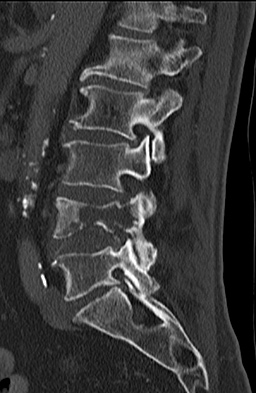

Figures 1 and 2 are CT scans obtained from a 68-year-old man who has had

progressive neck pain and stiffness, worsening gait imbalance, upper extremity weakness, early muscle fatigue, difficulty with fine motor control, and difficulty with activities of daily living over the past few years. On physical examination, he has a wide based stiff legged gait, generalized upper extremity weakness, dense sensory loss in the upper and lower extremities, and markedly brisk reflexes. What is the most appropriate treatment for this patient?

4. Posterior cervical laminoplasties from C3-6 Discussions: D

This patient has progressive myelopathy secondary to ossification of the posterior longitudinal ligament. Diagnostic imaging reveals multilevel cervical cord compression from C4-6. The patient has maintained reasonable cervical lordosis. A posterior procedure such as multilevel laminoplasty

decompresses the spine, is motion preserving, and has a low complication rate. Observation and cervical epidural injections are not viable options in patients with progressive myelopathy. Anterior cervical decompression, including corpectomy, is an option; however, anterior procedures have an increased risk of complications such as dural tear or cerebrospinal fluid leak. The axial CT image shows a "double layer" sign, which is consistent with dural ossification and increases the risk of dural injury with anterior decompression